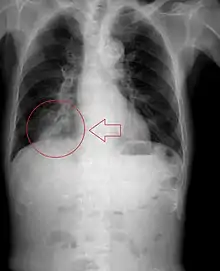

Pulmonary aspiration

Pulmonary aspiration is the entry of material such as pharyngeal secretions, food or drink, or stomach contents from the oropharynx or gastrointestinal tract, into the larynx (voice box) and lower respiratory tract, the portions of the respiratory system from the trachea (windpipe) to the lungs. A person may inhale the material, or it may be delivered into the tracheobronchial tree during positive pressure ventilation. When pulmonary aspiration occurs during eating and drinking, the aspirated material is often colloquially referred to as "going down the wrong pipe".

Consequences of pulmonary aspiration range from no injury at all, to chemical pneumonitis or pneumonia, to death within minutes from asphyxiation. These consequences depend on the volume, chemical composition, particle size, and presence of infectious agents in the aspirated material, and on the underlying health status of the person.

In healthy people, aspiration of small quantities of material is common and rarely results in disease or injury. People with significant underlying disease or injury are at greater risk for developing respiratory complications following pulmonary aspiration, especially hospitalized patients, because of certain factors such as depressed level of consciousness and impaired airway defenses (gag reflex and respiratory tract antimicrobial defense system). The lumen of the right main bronchus is more vertical and slightly wider than that of the left, so aspirated material is more likely to end up in this bronchus or one of its subsequent bifurcations.